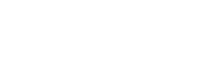

Bony defect from missing tooth for a long time. Patient underwent bone graft then ct scan to confirm adequate bone volume. Then implant placement.

The patient presented with a missing front tooth and a bridge he has been wearing for along time. CT scan taken showed insufficient bone to place an implant. A bone regeneration graft was performed. Post Graft ct scan showed excellent bone volume. A new implant was placed.